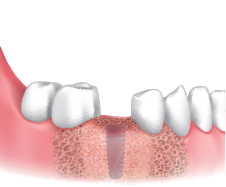

植入种植体后连接愈合基台,在缺损部位进行GBR。